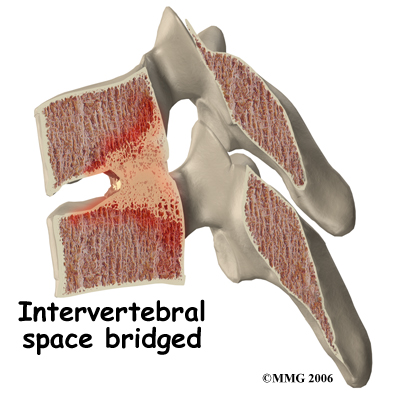

In some rheumatological diseases, the inflammatory process affects other areas of connective tissue such as where ligaments and tendons attach to the bone. This area is called an enthesis. There are entheses located all over the body with many in the spine itself, such as where the intervertebral disc attaches to the vertebra. Many of the rheumatological diseases that affect the spine seem to attack these particular areas of the spine but it is unclear why this occurs.

In some rheumatological diseases, the inflammatory process affects other areas of connective tissue such as where ligaments and tendons attach to the bone. This area is called an enthesis. There are entheses located all over the body with many in the spine itself, such as where the intervertebral disc attaches to the vertebra. Many of the rheumatological diseases that affect the spine seem to attack these particular areas of the spine but it is unclear why this occurs.

In some rheumatological diseases, the inflammatory process affects other areas of connective tissue such as where ligaments and tendons attach to the bone. This area is called an enthesis. There are entheses located all over the body with many in the spine itself, such as where the intervertebral disc attaches to the vertebra. Many of the rheumatological diseases that affect the spine seem to attack these particular areas of the spine but it is unclear why this occurs.

In some rheumatological diseases, the inflammatory process affects other areas of connective tissue such as where ligaments and tendons attach to the bone. This area is called an enthesis. There are entheses located all over the body with many in the spine itself, such as where the intervertebral disc attaches to the vertebra. Many of the rheumatological diseases that affect the spine seem to attack these particular areas of the spine but it is unclear why this occurs.